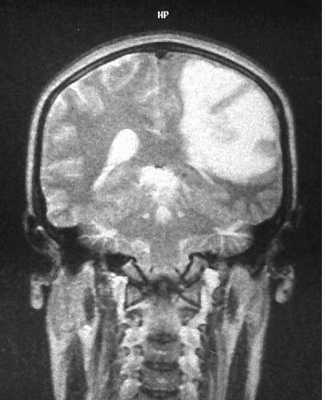

При МРТ доброкачественные астроцитомы чаще выглядят однородными, хотя возможна неоднородность в связи с кальцинатами (до 20% случаев) и микрокистозной дегенерацией. Границы опухоли четкие. Вазогенный отек выражен только при низкодифференцированном подтипе. Астроцитома может вовлекать кору мозга и напоминать острый ишемический инсульт. Различать их при МРТ помогает отчетливо клиновидная форма при инсульте, совпадающая с бассейном кровоснабжения. Нередко при МРТ головного мозга встречаются “кистозные” астроцитомы, когда сама опухоль имеет небольшие размеры, а прилежащая ликворная киста значительно больше ее самой. Анапластические астроцитомы на МРТ хорошо усиливаются при контрастировании, доброкачественные астроцитомы усиливаются при МРТ с контрастированием примерно в 40% случаев. Изредка встречаются первично-множественные астроцитомы. Гигантоклеточная внутрижелудочковая астроцитома встречается только при туберозном склерозе. При МРТ она имеет типичное расположение и хорошо контрастируется.

МРТ головного мозга. Туберозный склероз. Гигантоклеточная внутрижелудочковая астроцитома (стрелки). Прорастание в хвостатое ядро. Окклюзия отверстия Монро. Т2-зависимая, Т1-зависимая и Т1-зависимая с контрастированием аксиальные МРТ.